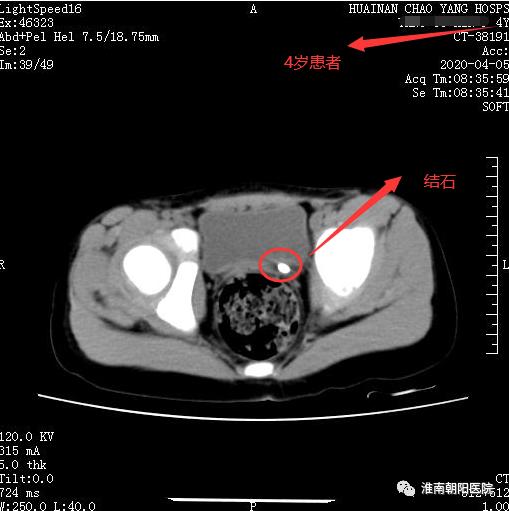

近年淮南朝阳医院在淮南市率先引进小儿输尿管镜,对于儿童输尿管结石和输尿管狭窄的患者手术治疗提供了更安全的保障。很多患有结石的小天使们通过微创技术解除了疾病的困扰,消除了疾病对身体和心理造成影响,守护了孩子的健康与童真。

不久前,一位 4 岁小朋友患有输尿管结石,家人本来打算去上海治疗,后来听说淮南朝阳医院泌尿外科的微创技术,于是住院治疗。入院后患儿体温最高 39℃,在完善术前检查和抗感染治疗稳定的基础上,邓大溢副院长坐镇指导,方强副主任医师娴熟的应用输尿管镜钬激光碎石技术顺利粉末化结石,解除了梗阻,患儿顺利出院。

术前情况